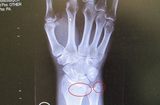

Apr 28 The story of how I broke my wrist, and dealing with it.